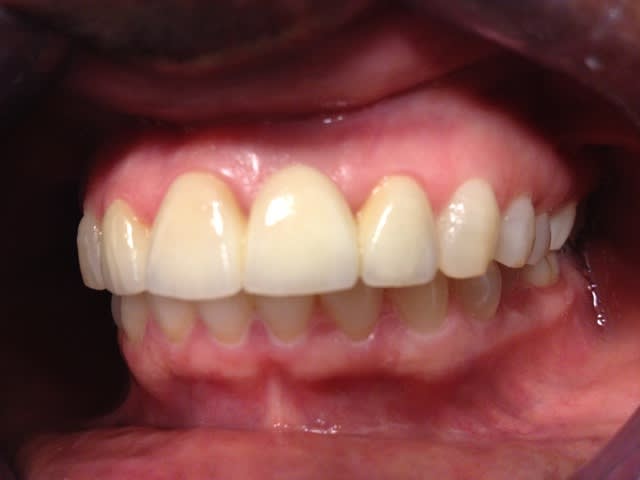

10/07/2012 à 23h01

Je déterre mon poste en mettant les photos du cas. Désolé il manque le principal: la photo de l'état initial...

Je n'ai pas osé faire que de l'Emax. J'ai décidé avec le labo de faire une armature Zircone avec de l'Emax pressée dessus.

Il y a les photos du biscuit, du bridge fini le jour de la pose et à 3 semaines.

A vos critiques, merci!

10/07/2012 à 23h39

C'est très beau.

De ce que l'on peut en voir, c'est beau et propre.

je trouve le résultat très esthétique ;)